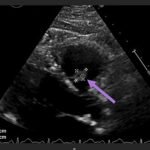

Endovascular coil embolization continues to become a more frequent modality of addressing hemorrhage and bleeding in patients. Migration refers to the coil unraveling or moving from the original embolization site. Migration of a coil is a known complication which can lead to serious consequences based on where the coil migrates. Despite increasing efforts to improve safety and technique, the risk of migration remains. We present a case of an embolization coil that migrated to the right ventricle, which was incidentally found roughly 2 months after undergoing an interventional radiology procedure for gastric variceal bleeding. The patient presented to the emergency department with dyspnea and abdominal pain. Unique images were obtained during his visit and in subsequent follow-up. As use of vascular embolization coils continues to become more commonplace, understanding the risks and complications of these procedures remains an important aspect of providing care for patients once they have left the interventional radiology suite. Coil migration should be a differential to consider in patients who present to the emergency department with signs or symptoms of arrhythmia or pulmonary embolism who have undergone a coil embolization procedure.